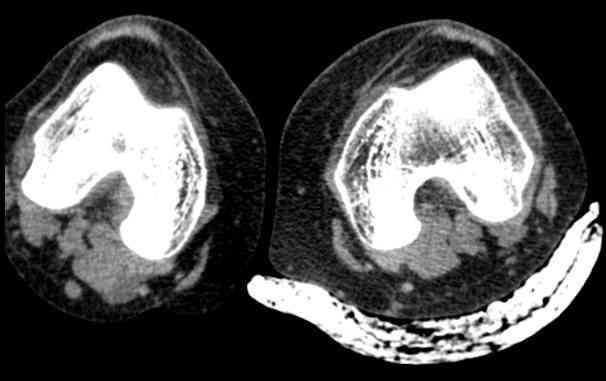

привычный вывих надколенника + patella alta

Обратилась молодая женщина с повторным вывихом надколенника, повторный вывих в октябре 2013. после чего находилась в гипсе и ортезе. Сейчас сгибание - 90. Снимки прилагаю. Планирую латеральный релиз и medial plication. Достаточно ли этого будет? Другие варианты?